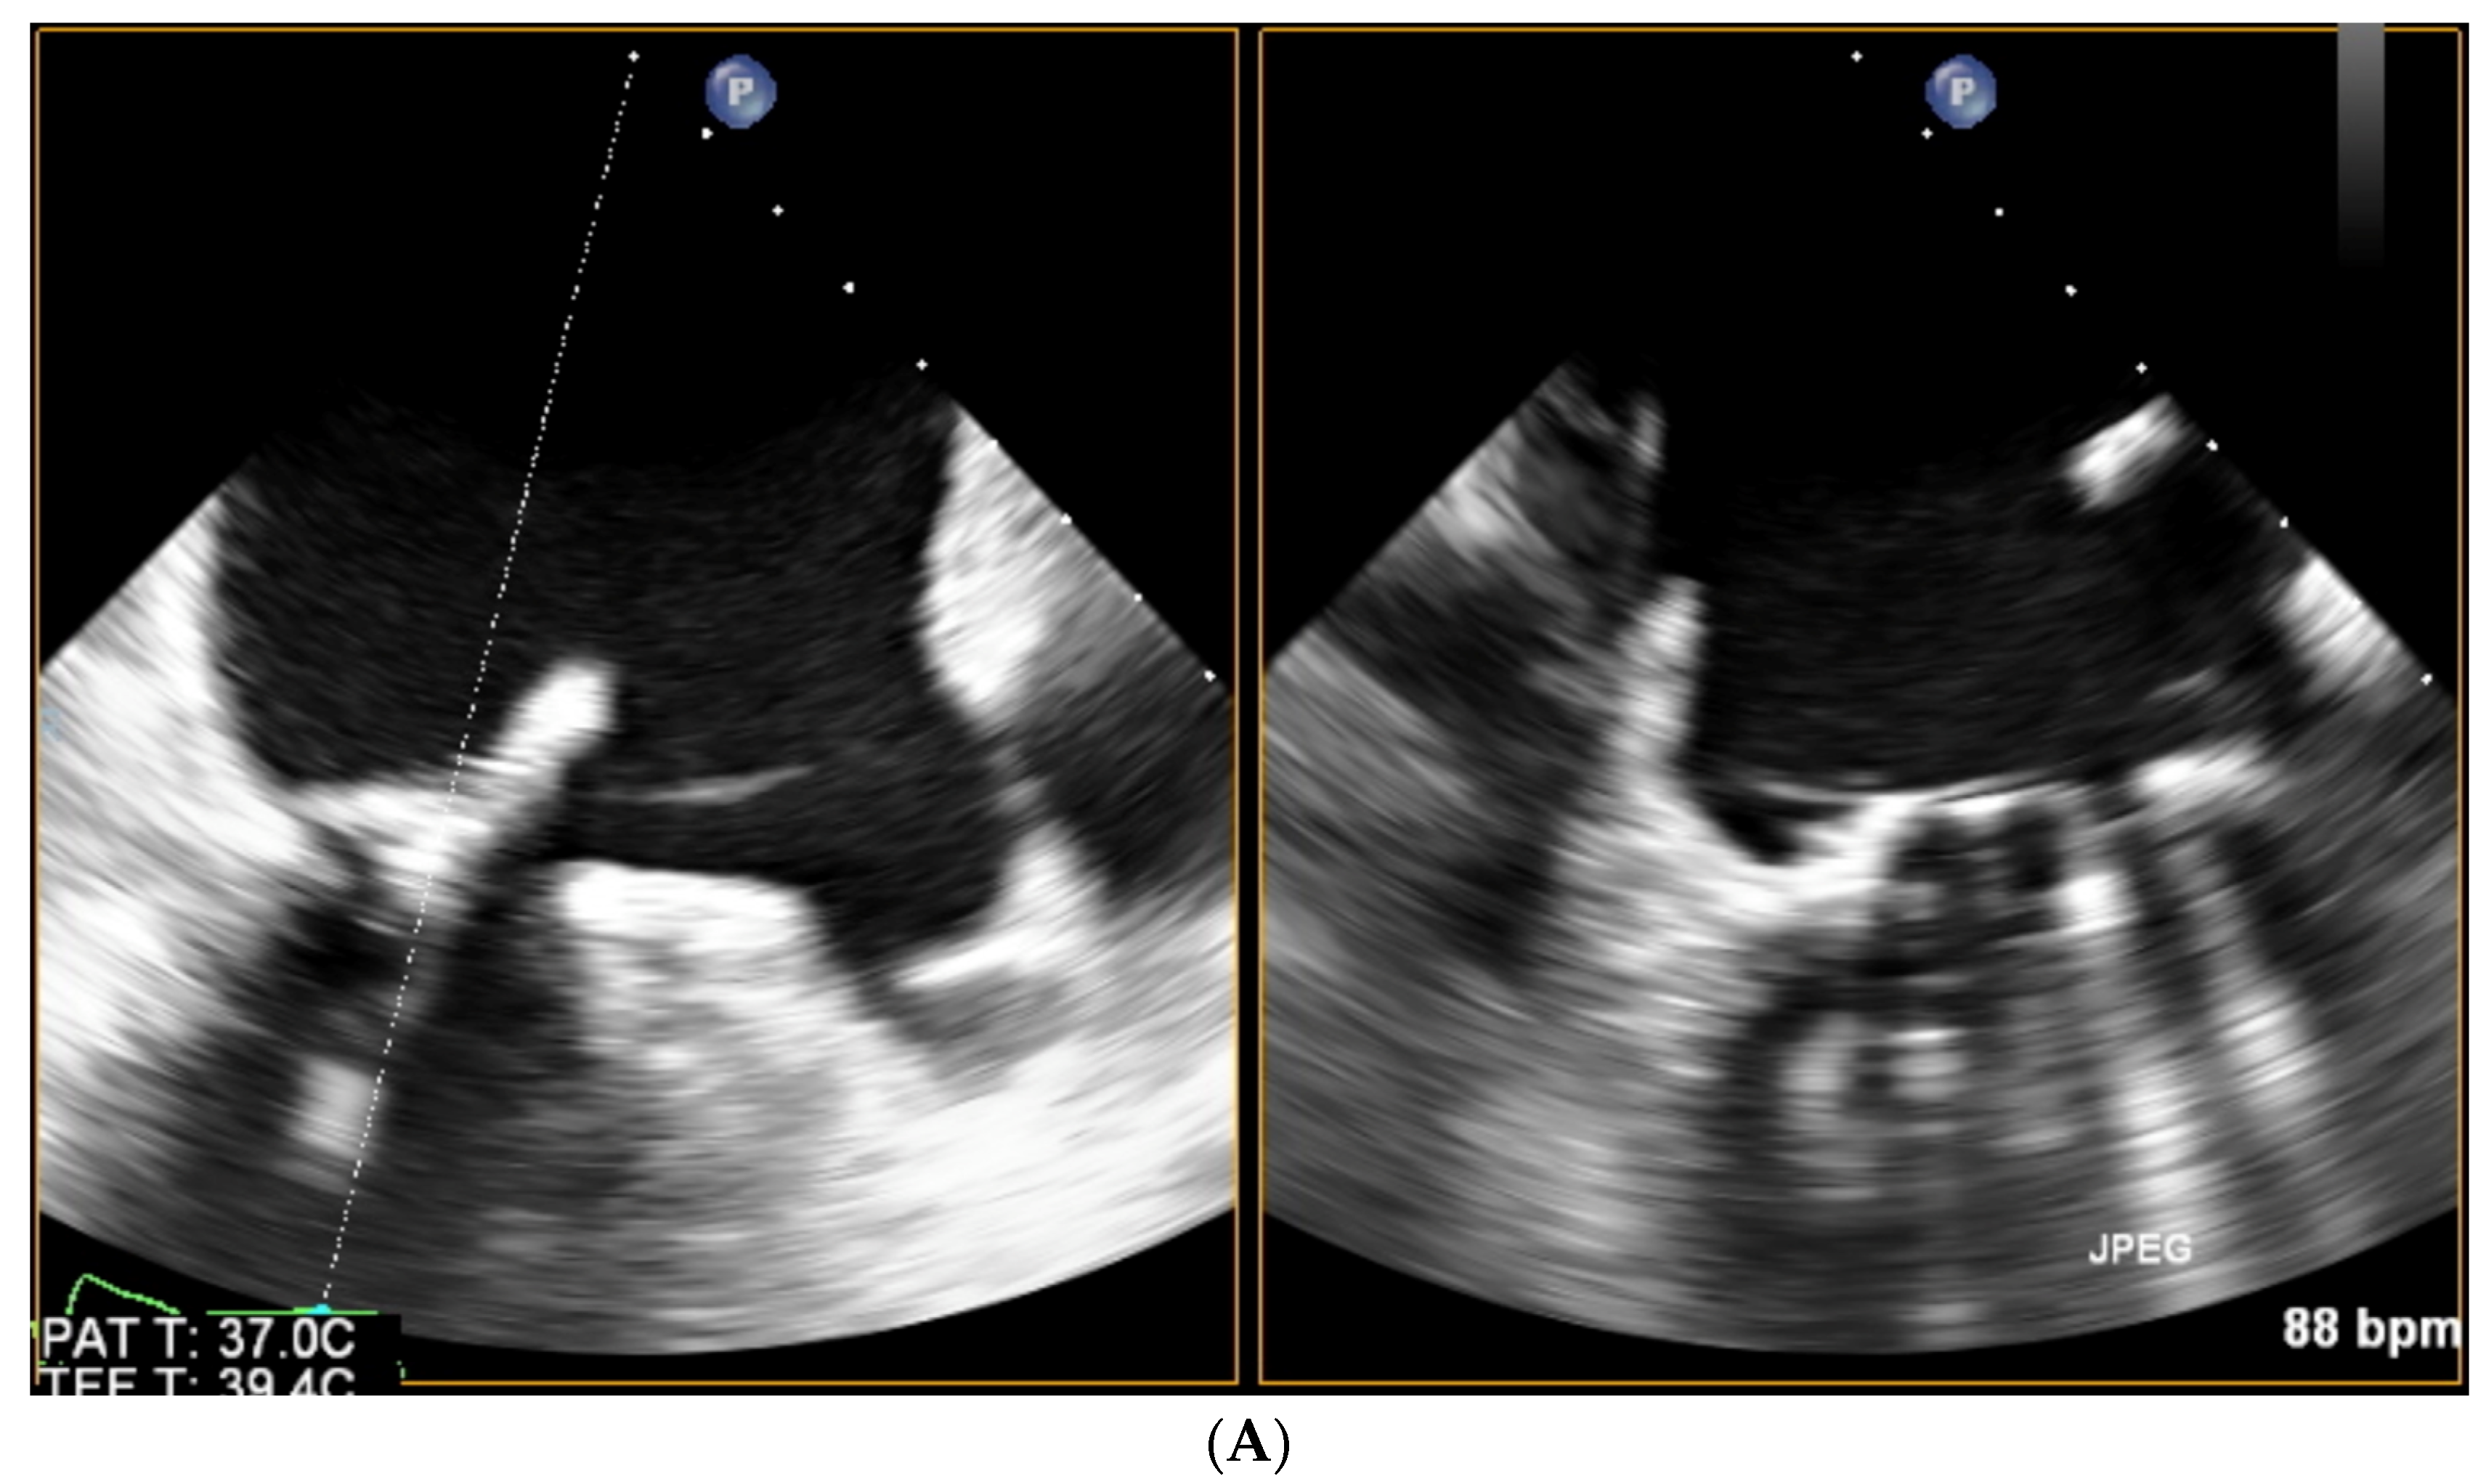

For mitral PVLs, the choice of a transseptal puncture site should be driven by the location of the channel, as such an approach greatly enhances the chances of successful crossing. Ideally, echo guidance should offer biplane imaging, with two perpendicular planes simultaneously visible side by side (without the need for repetitive switching between bicaval and short-axis views). While tenting produced by the transseptal sheath is visualized in the center of both images, its location can be further optimized. See Figure 3.

The directions of motion are identified in a standard manner in regard to the superior (SVC) and inferior (IVC) vena cava (superior: towards the SVC; inferior: towards the IVC) and aorta (anterior: toward the aorta; posterior: opposite the aorta). Increasingly, in selected patients, intuitive guidance by 3D volume rendering is possible. See Figure 4.

Figure 3. Biplanar imaging of the interatrial septum tenting produced by the tip of the transseptal sheath.

Figure 4. 3D TOE volume rendering visualization of the interatrial septum tenting (black arrow) produced by the tip of transseptal sheath (IVC: inferior vena cava; Ao: aortic root).